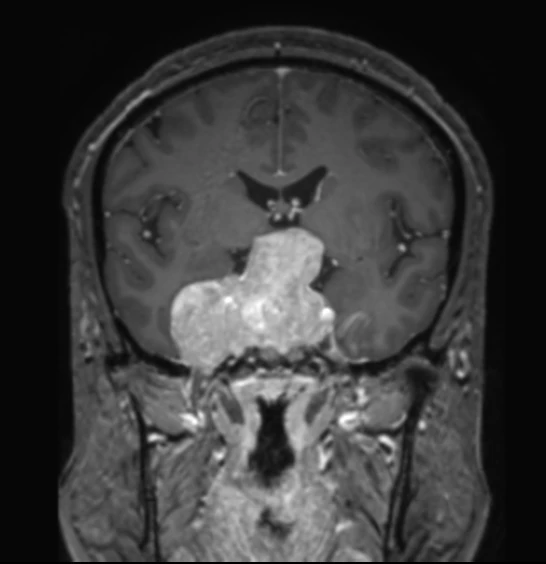

Снеговики бывают разные, но смысл симптома при аденоме гипофиза от этого не меняется: когда опухоль растёт вверх, она протискивается черезу дуральную селлярную диафрагму и в этом месте на ней явственно определяется поясок. Это, как утверждается, достаточно надёжный дифференциально диагностический признак (точность порядка 94-96%) именно аденомы гипофиза, а не какой-то другой опухоли данного расположения.